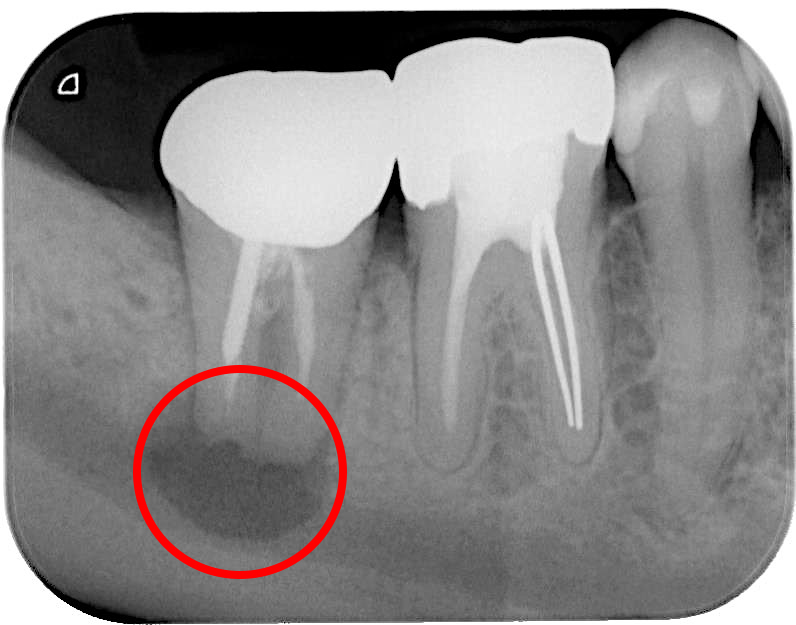

• 治療前

• 治療後

根の先に大きな膿の袋ができ、歯茎の腫れと痛みを繰り返してきた症例。

当院で根管治療を行い、MTAセメントを充てんし、病変は治癒した。